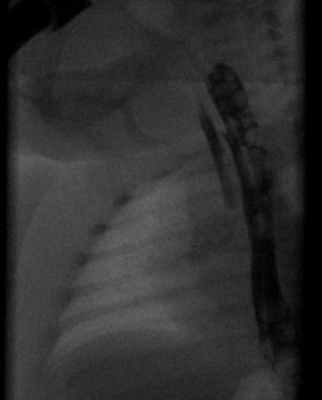

Рентгенограмма с пероральным контрастным веществом, показывающая трахео-пищеводный свищ h-типа у новорожденного

Следует подозревать ТЭФ, если ребенок не может глотать после первого кормления в течение первого дня жизни. Атрезию пищевода можно диагностировать с помощью назогастрального зонда Райла; если Райл не может пройти в желудок, это указывает на атрезию пищевода и потерю связи между желудком и пищеводом. ТЭФ можно диагностировать с помощью МРТ, которая уточняет атретический отдел пищевода (если имеется) и ТЭФ, а также его расположение и анатомию. При подозрении на ТЭФ нельзя использовать проглатывание контрастного вещества с гастрографином из-за высокого риска аллергии и тяжелой трудноизлечимой инфекции грудной клетки. [ нужна цитата ]